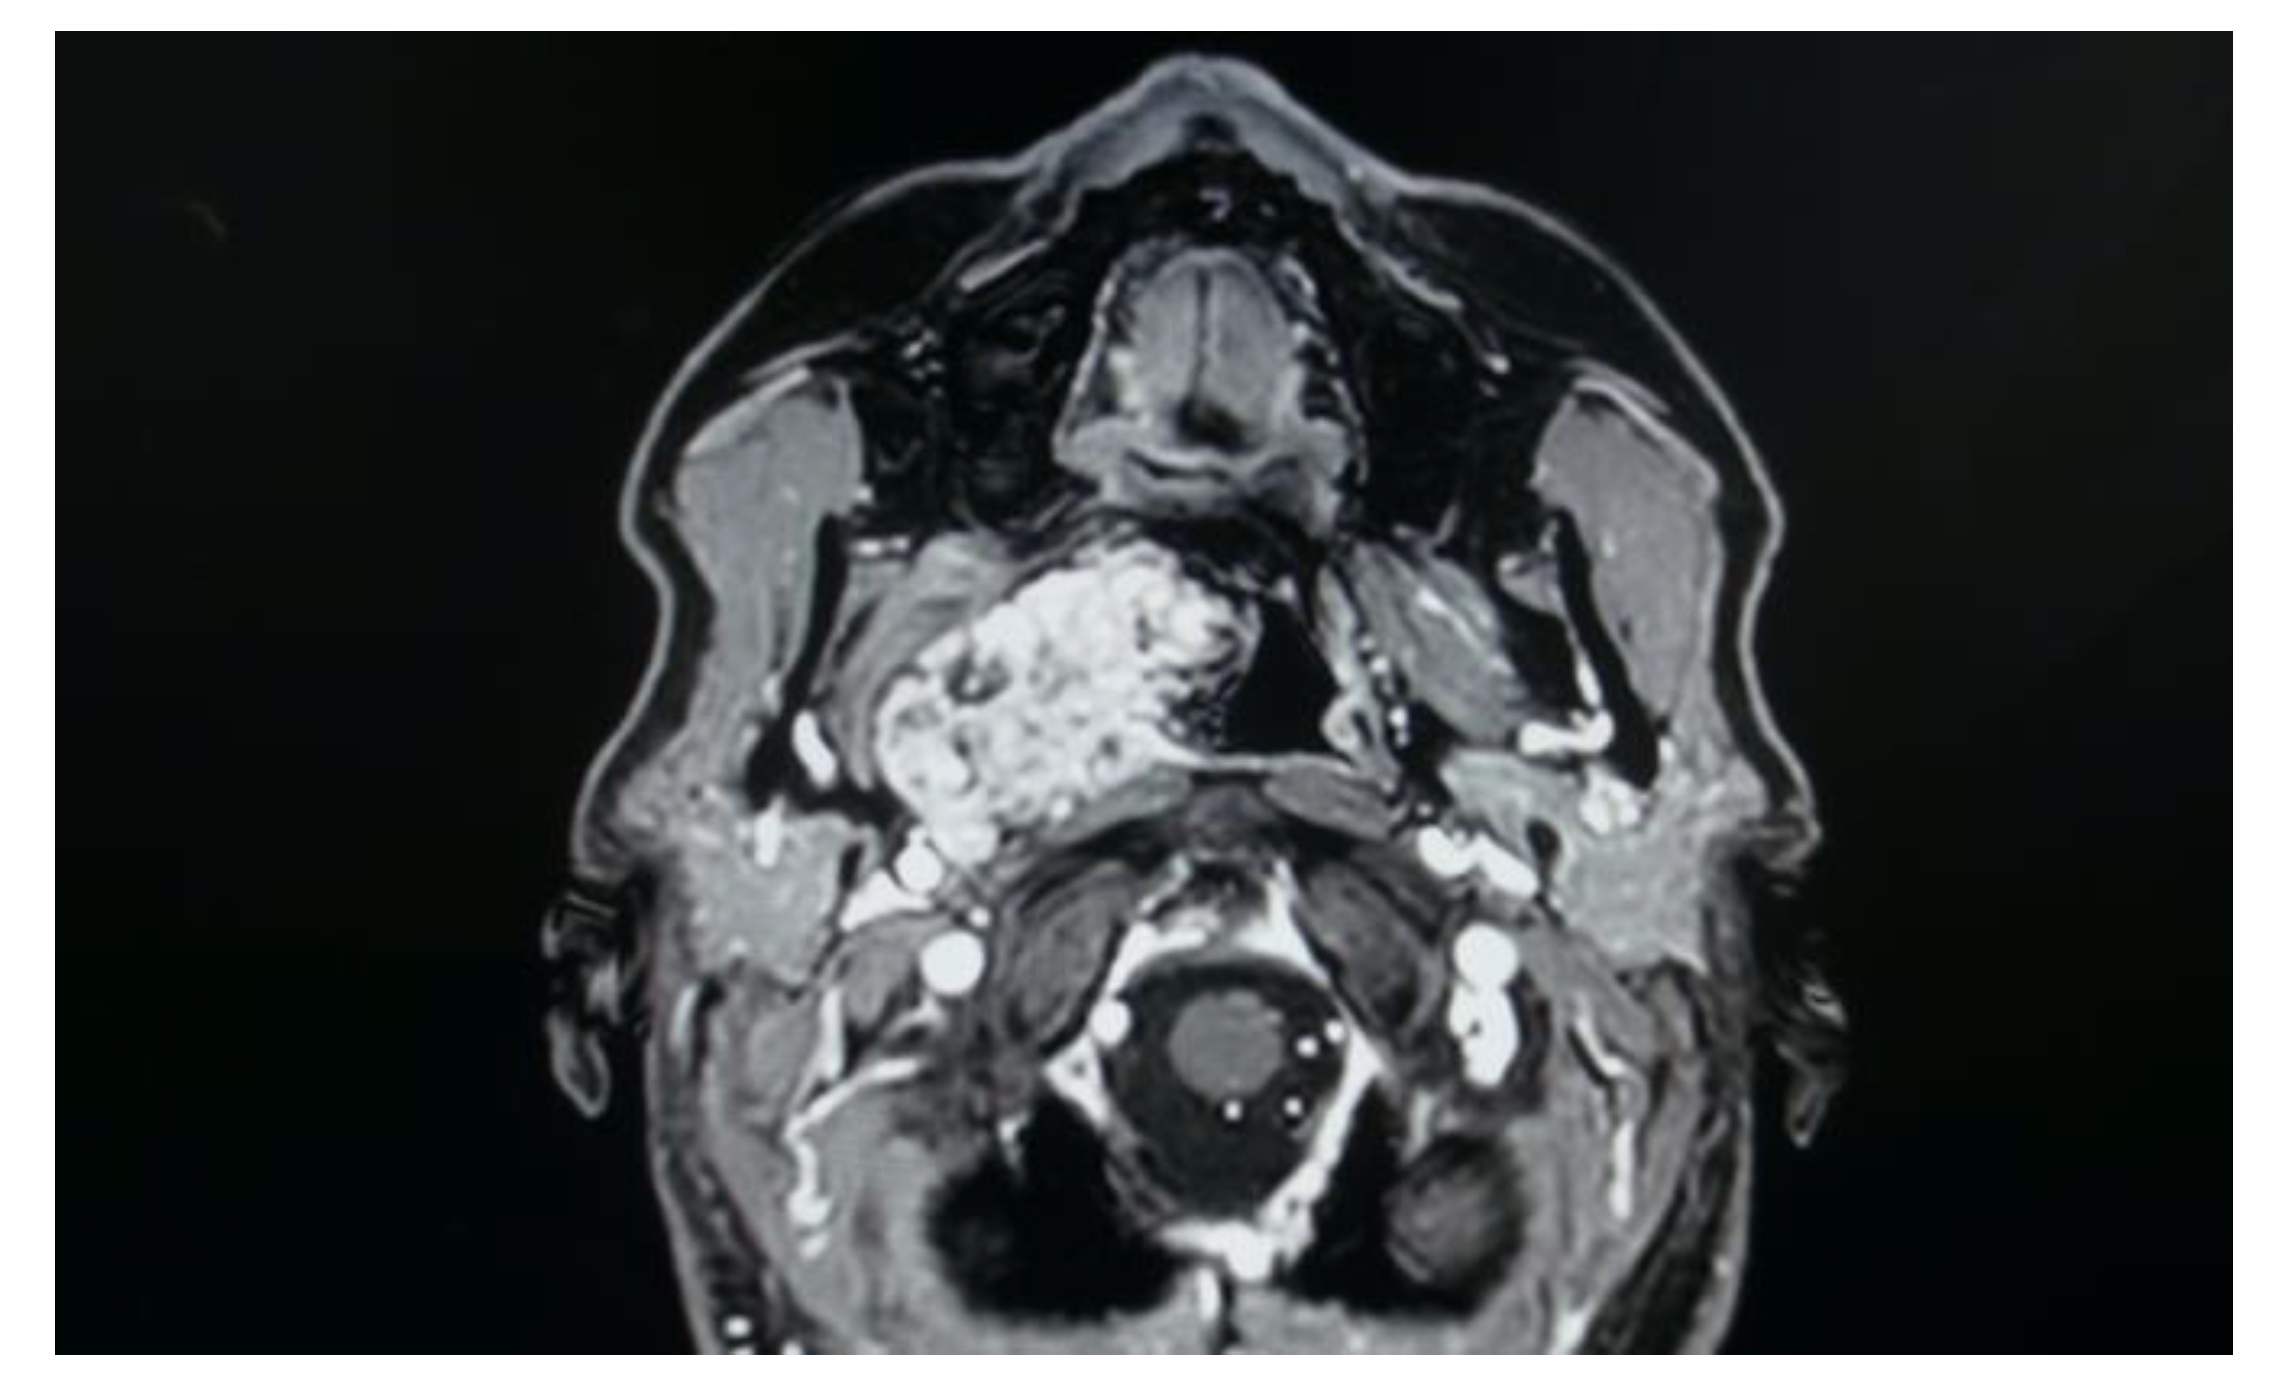

- Five pleomorphic adenomas that arose from minor salivary glands in three cases and from the deep lobe of the parotid gland in two cases. All of these tumours were situated in the true PPS, medially with respect to the great vessels. In all the patients, no complications were observed during and after surgery. Hospitalisation time was two days for three patients, three days for one patient and four days for the other patient. No tumour recurrence was observed after sixteen, nine, eight and seven years for the first four patients. Evaluating the recurrence in the last patient is still not possible due to the short follow-up period, since the patient underwent surgery in 2021.

- One lipoma arose from the true parapharyngeal space. The patient underwent surgery in 2012 and had no intraoperative and no postoperative complications. No recurrence was observed after ten years. The hospitalisation time was two days.

- One ectopic thyroid arose from the right true parapharyngeal space. This was the only case in which a fine needle aspiration citology (FNAC) was performed, and the results were inconclusive. The patient underwent surgery in 2003 with no intraoperative or postoperative complications. The hospitalisation time was three days. No recurrence observed after eighteen years.

- Two schwannomas (Figure 5) originating from the cervical sympathetic chain and that arose in the superomedial aspect of the PPS, medially to the carotid sheath. The first patient underwent surgery in 2008, the second in 2019. No complications were observed during surgery and no tumour recurrence has been observed after 14 and 4 years, respectively. The only long-term complication observed was Horner syndrome (Figure 6), despite the continuity of the nerve not being interrupted. The hospitalisation time was three days for both patients.